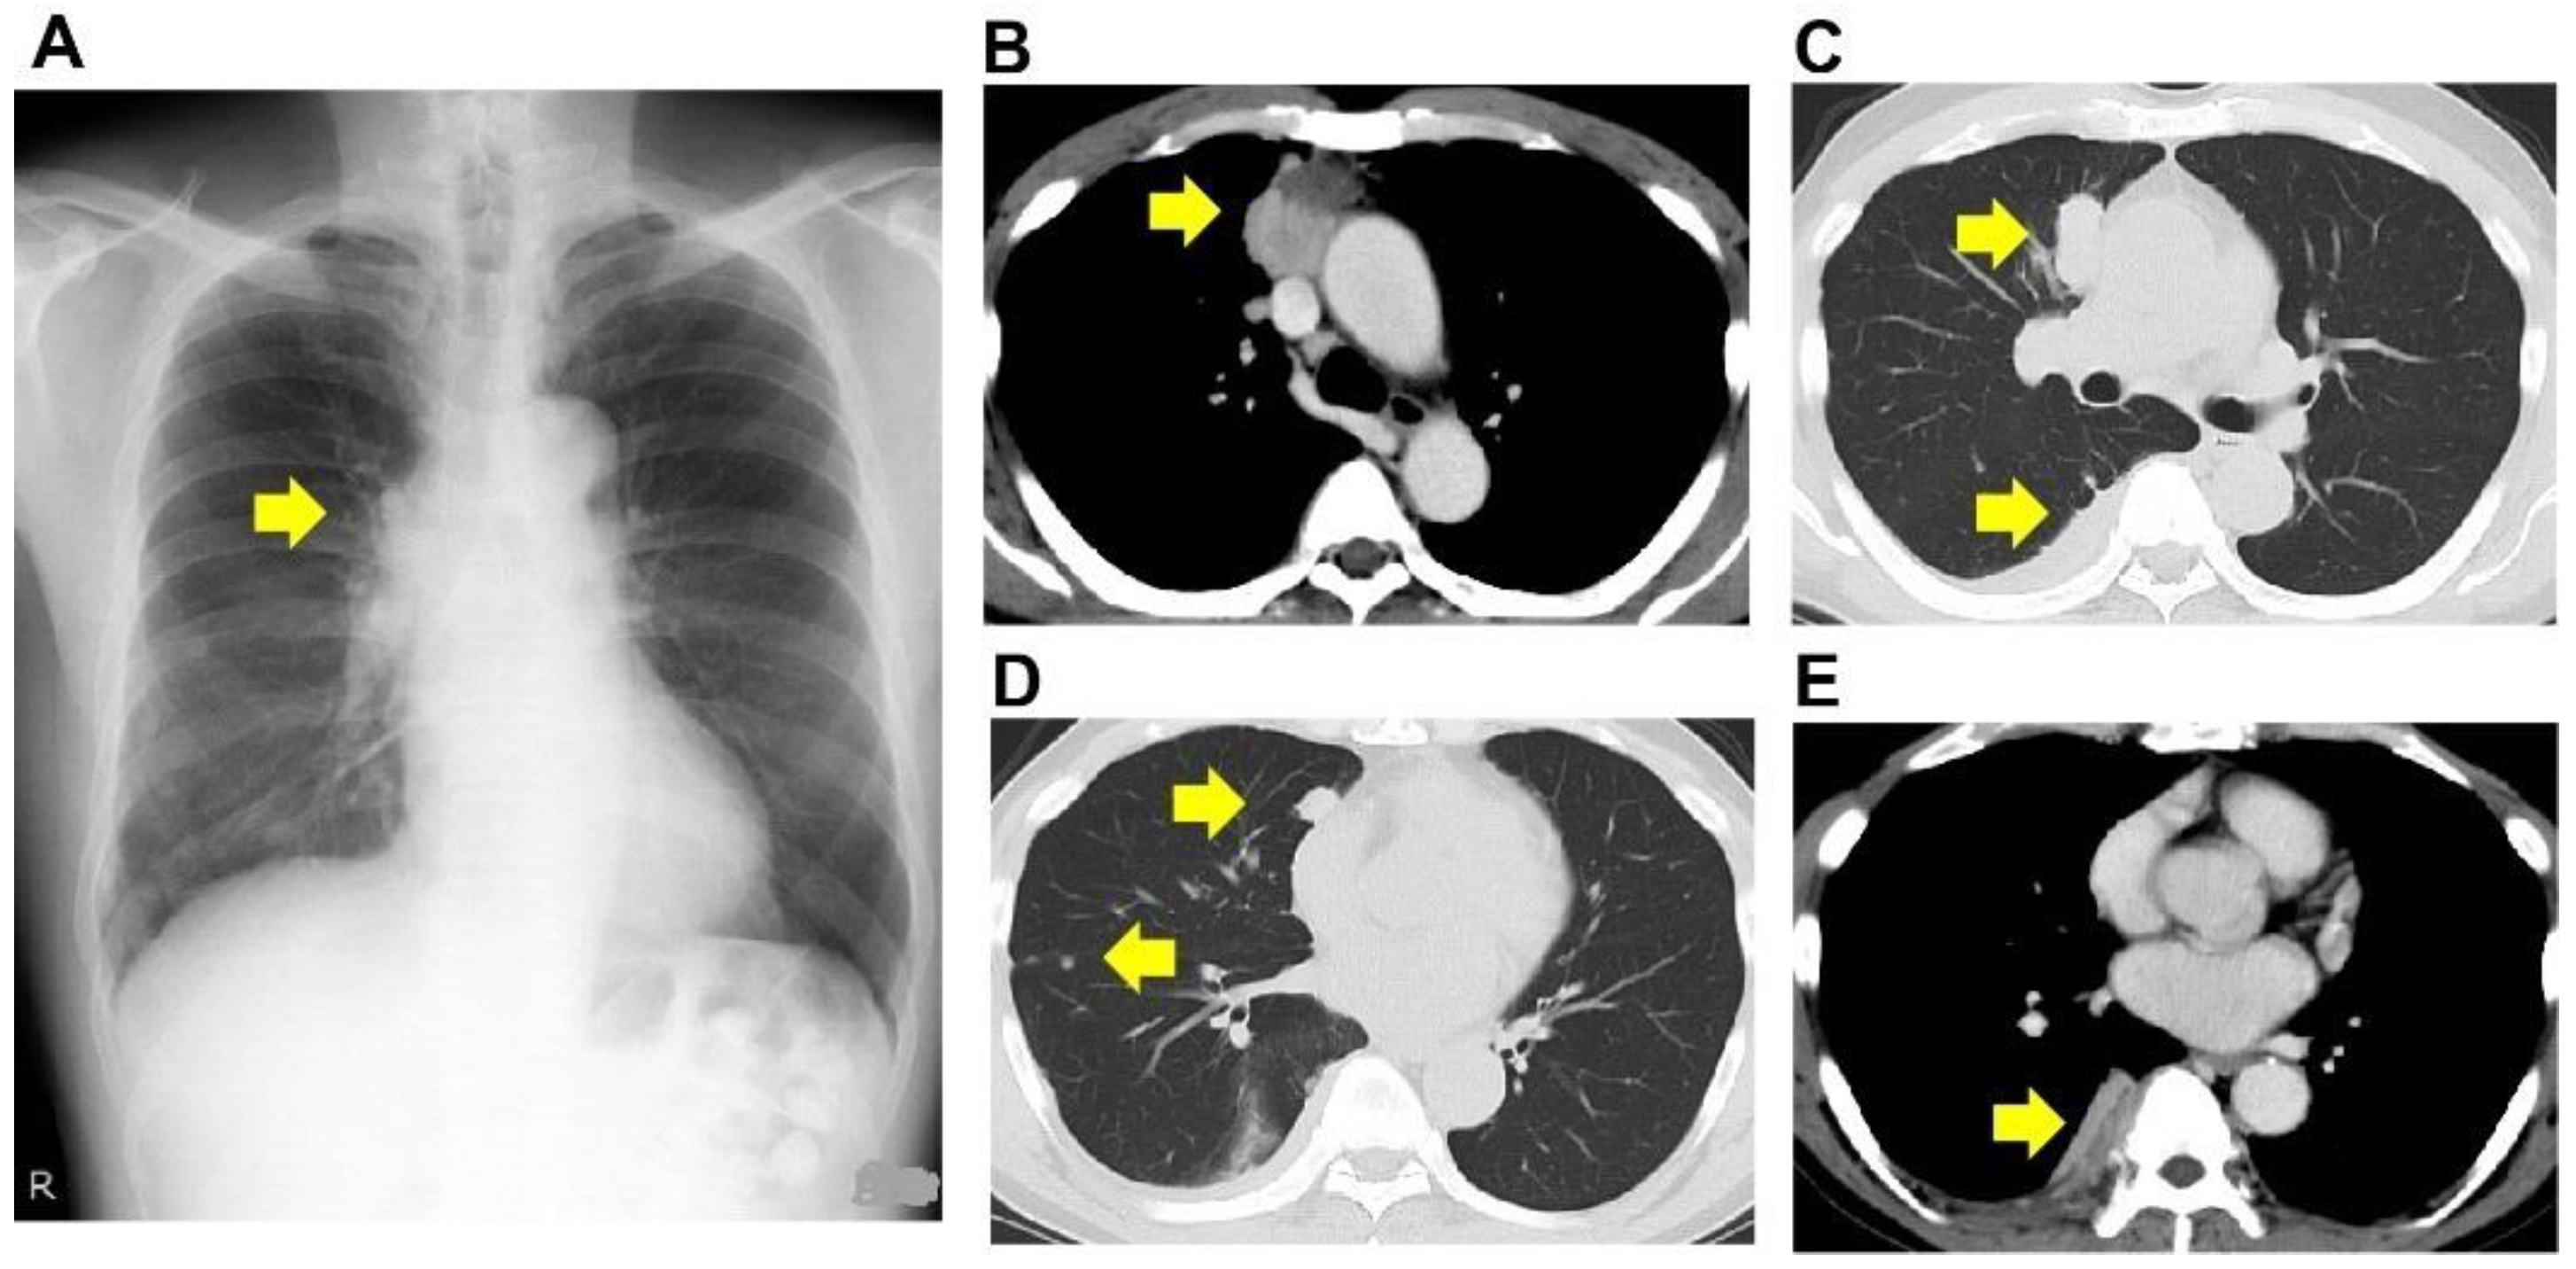

The patient was a 64-year-old male and ex-smoker. The patient was a smoker (20 cigarettes per day) between the ages of 20 and 25. He was being treated for bronchial asthma with inhaled corticosteroids and long-acting beta-agonists. His Eastern Cooperative Oncology Group Performance Status score was 0. He was referred to our institution for an abnormal shadow on the chest X-ray taken during a routine medical check-up. He had no symptoms, and the routine laboratory examination showed normal findings. He had no occupational or environmental exposure to any noxious agent. The computed tomography (CT) study showed a tumor between the anterior mediastinum and the right lung upper lobe, multiple nodular shadows along the right pleura, and pleural effusion (Figure 1A–E).

Figure 1.

Radiological findings. Plain radiograph (A) and computed tomography (B–E). The computed tomography revealed a tumor between the anterior mediastinum and the right lung upper lobe (B,C), multiple nodular shadows along the right pleura (D), and pleural effusion (E). Arrows indicate the lesion.